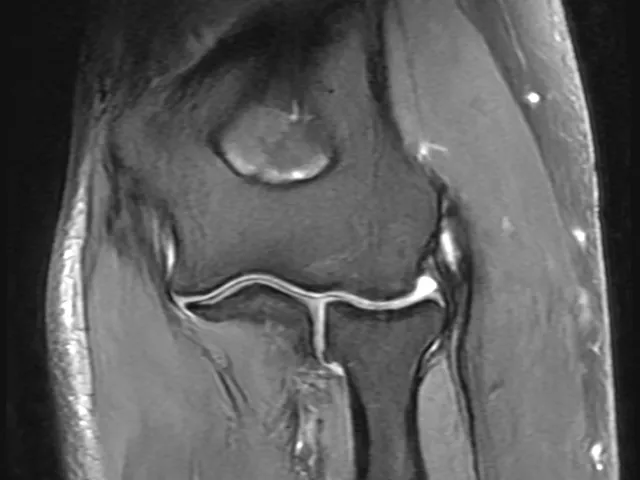

This Upper Extremity musculoskeletal (MSK) MRI course, taught by highly knowledgeable radiologist Phillip Tirman MD, will include an overview of MRI of the shoulder, elbow, arm and forearm, wrist, and hand with a daily presentation, individual case readings, and with group-based case read-outs.

With years of experience in the field of MSK radiology, Dr. Tirman comes prepared with his own case mix to share with you, containing a large variety of musculoskeletal cases relevant to the topic which participants can also review on their own after the fellowship.

Each day of the fellowship starts with a lecture followed by the challenge of practicing on real anonymized illustrative cases from the personal file of Dr. Tirman and then finished with a group discussion of the cases. Radiologists who would like to become more confident with the interpretation of imaging of MSK MRI will find this fellowship useful.

- Become familiar and feel confident with performing Standard MRI and MR Arthrography related to MSK MRI imaging as encountered in daily practice.